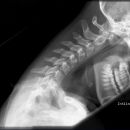

Funktionsaufnahme der HWS

Es wurden keine Bilder gefunden.

Kassette/Abstand

Format 24/30 quer für Inklination, 18/24 hoch für Reklination / FFA 1,15m

Lagerung

Patient seitlich gegen Wandstativ stellen, möglichst Gewichte in die Hände geben.

Inklination:

Patient beugt Kopf soweit wie möglich auf die Brust.

Reklination:

Patient beugt Kopf soweit wie möglich nach hinten. Achtung: WS muss über der Messkammer liegen!

Zentralstrahl

Senkrecht auf Objekt- und Filmmitte.

Qualitätskriterien

Orthograde, streng seitliche Abbildung der Grund- und Deckplatten der HWS. Alle 7 HWK in maximaler Inklination bzw. Reklination.